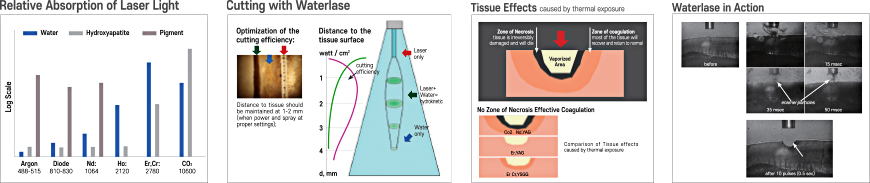

Waterlase

The Waterlase is cleared by the FDA for more than 20 periodontal indications

- Effective cleaning of contaminated implant surfaces

- No thermal damage to surrounding tissues

- Highly effective against bacterial infections

- No damage to the implant surface

- Promotes osseointegration and bone regeneration